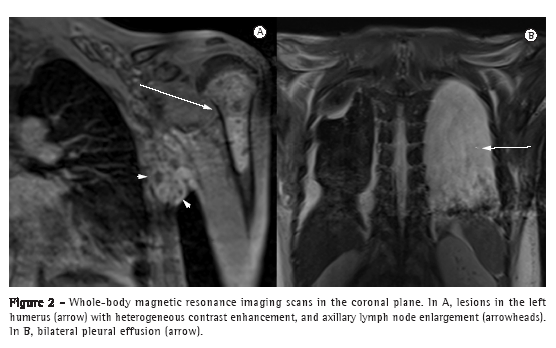

On T1-weighted images, the skeletal lesions varied from hypointense to isointense, exhibiting, at some sites, cortical bone destruction and an extensive soft tissue component. In a gadolinium-enhanced VIBE sequence with fat suppression, the lesions exhibited an insufflating pattern, with contrast enhancement predominantly in the peripheral regions (Figures 1B and 2A). On a STIR sequence, the central portions of the lesions presented hyperintense signals, suggestive of necrotic tissue.

Whole-body MRI with STIR sequences also revealed pleural and peritoneal involvement, manifesting as pleural effusion and ascites, as evidenced by a typical hyperintense signal (Figure 2B). There were no other sites of involvement.